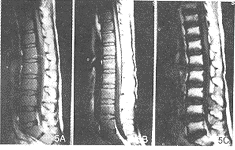

急性白血病组: T1WI: (1)治疗前组38例:腰骶椎38例所有椎体均表现为均匀的信号降低,比相邻的椎间盘和脊髓的信号均明显降低;髂骨38例均表现为低信号,其中3例于髋臼旁见斑片状高信号残留;股骨近段信号降低38例,其中8例股骨头、股骨大转子见斑片状高信号残留,且此8例均有骨骺板存在。 (2)化疗缓解组25例:所有椎体、髂骨、股骨头、股骨大转子及骨干均表现为不同程度的信号增高,达完全缓解者(21例)比部分缓解者(4例)更接近相应的正常骨髓信号(图3、4)。其中9例还作了治疗后追踪观察,第1次为化疗1疗程结束5天内并经临床及骨髓穿刺认为完全缓解时行MRI检查,第2次为2~4周内经骨髓穿刺后行MRI检查。6例2次经骨髓穿刺检查均为完全缓解,但第2次MRI检查椎体信号比第1次略为增高(图5)。复发的3例中,2例再次缓解,经MRI检查,其骨髓信号重新升高。

图3 男,11岁。急性白血病。T1WI示:A.治疗前椎体呈均匀低信号,椎体形态正常;B.治疗后完全缓解其椎体信号明显升高 图4 同图3病例。T1WI示:A.治疗前髂骨、股骨上段信号明显降低;B.治疗后完全缓解其信号升高 图5 17岁。急性白血病。T1WI示:A.治疗前椎体均匀低信号;B.治疗后缓解2天,椎体信号稍升高;C.治疗后缓解3周,椎体信号明显升高